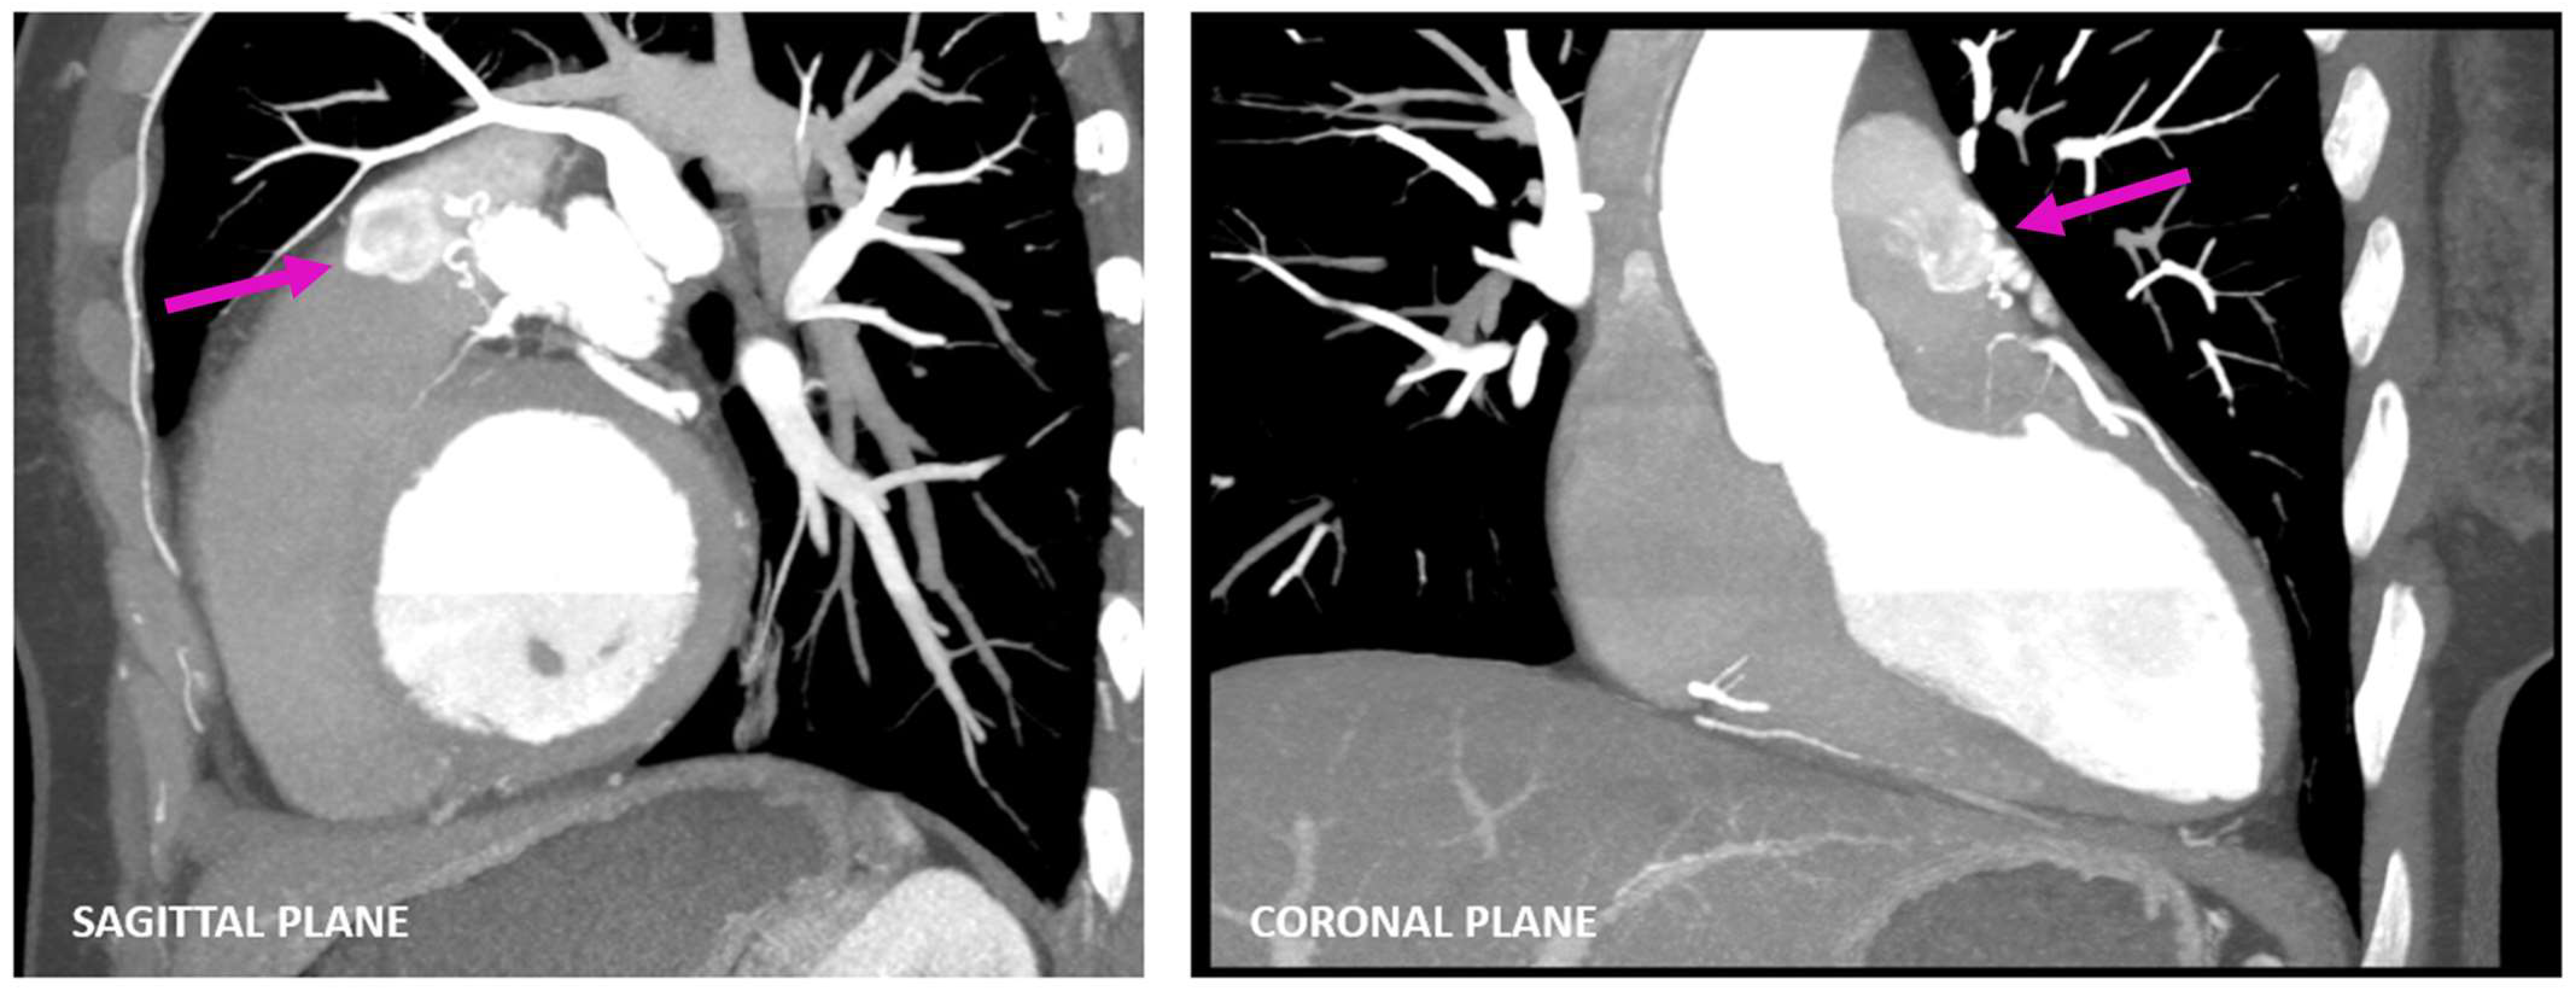

A Rare Case of Left Anterior Descending Coronary Artery to Pulmonary Trunk Fistula Associated with Takotsubo Cardiomyopathy